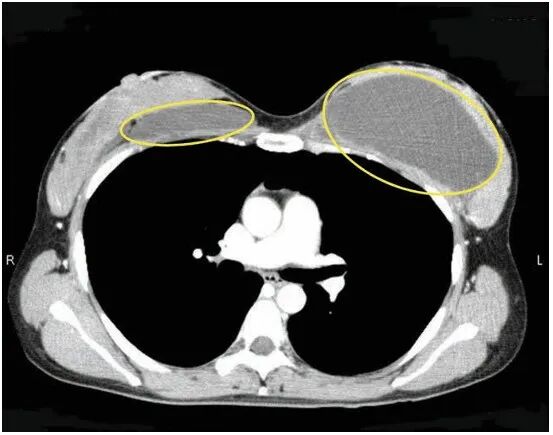

自体脂肪隆胸是计算好左右侧乳房注射量后,在双侧乳房外侧用直径2毫米注射针,将抽吸的颗粒脂肪注射到乳房的腺体的深面,胸大肌表面。一般一次自体脂肪隆胸手术注射量为每侧30-150毫升,局部按摩使脂肪分布均匀,达到理想的塑形。根据患者的要求大小,一般注射2-3次,每次相隔2-6个月,能达到所有要求的乳房体积大小和形态,最大每侧可增加280-300毫升,通常120-220毫升。

最后就是要自体丰胸手术了,前面都是在为自体丰胸手术做准备,接下来看如何自体脂肪如何丰胸了,移植颗粒脂肪使用14-16号长针头从腋下或肚脐注射颗粒脂肪到胸部内,必需均匀分布在皮肤下.乳腺腺体外围和胸肌下空间(每侧约100- 150c.c),严厉要求每一单点移植脂肪颗粒小于 0.5c.c,并禁止注入乳腺体内,随后马上推拿塑型与绷带爱护。这是自体脂肪丰胸手术过程的第三步。